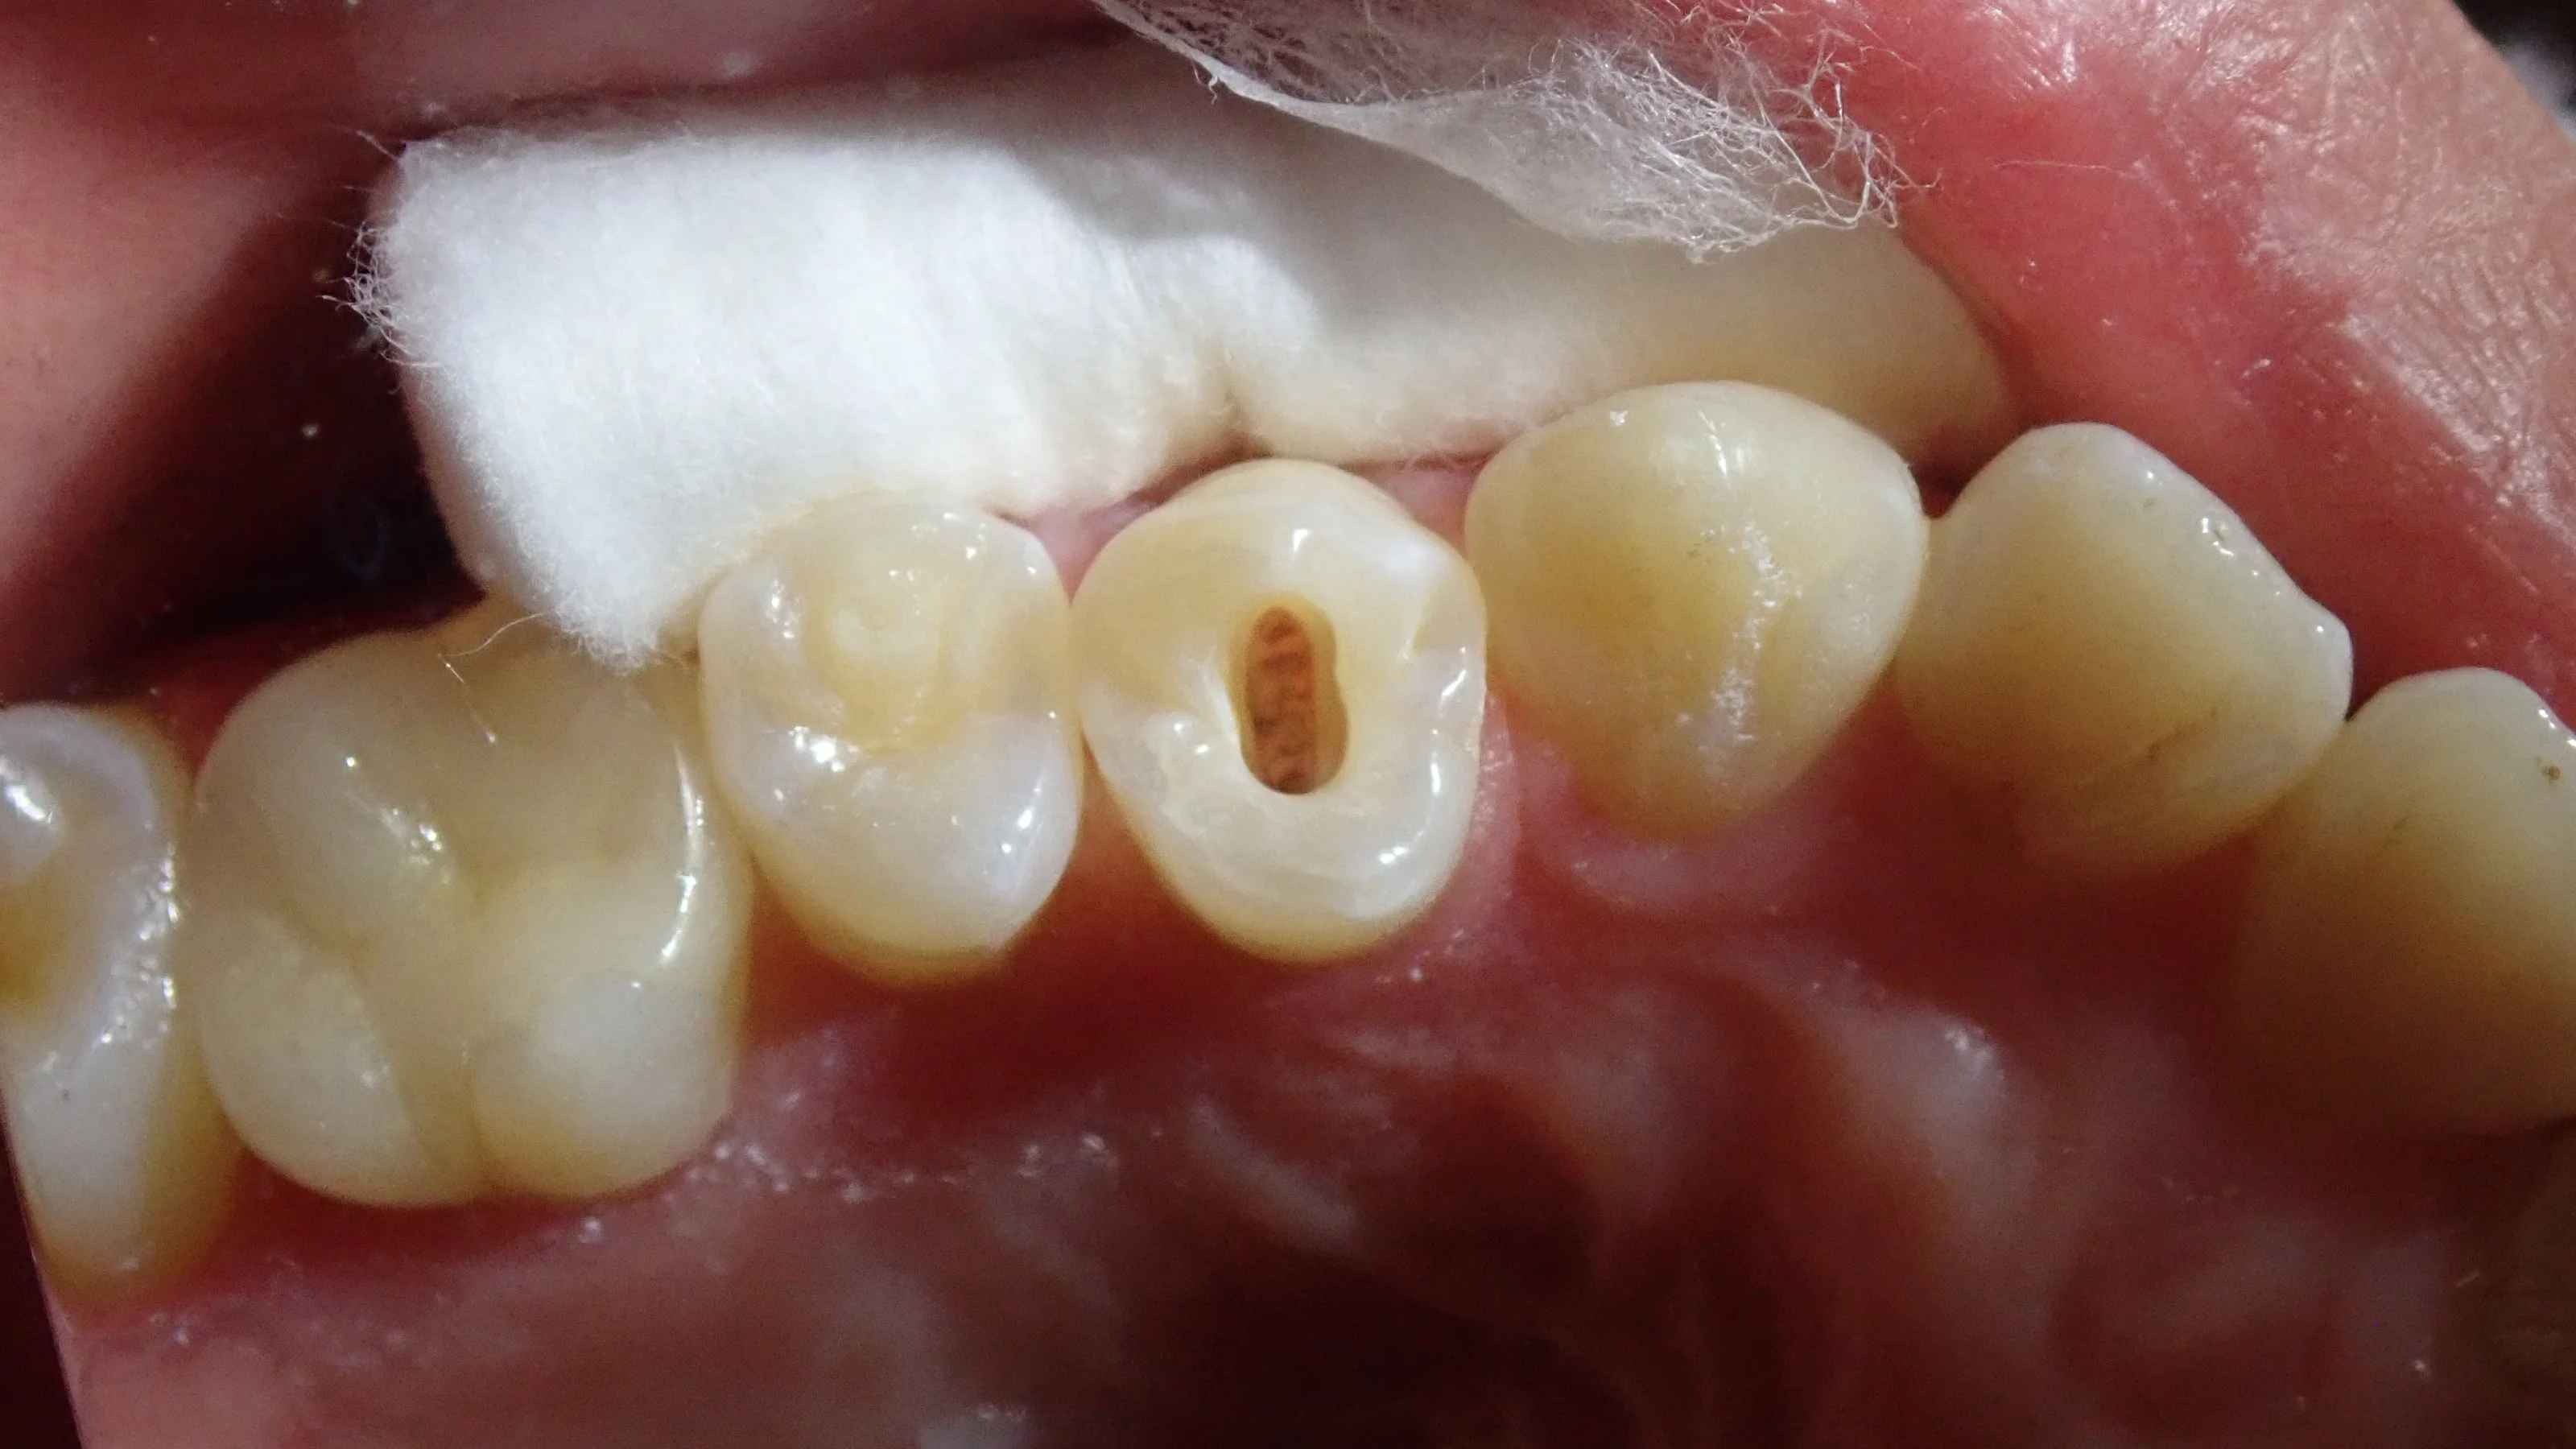

元々中心結節が折れることで感染を起こした状態でしたので、無駄に歯を削ったり、被せ物を入れたりする必要はありませんでした。

なので、こんな感じで、最小限の歯質削除を行って、神経の治療を行っていきました。

そして、最終的に詰め終わったのがこちら。